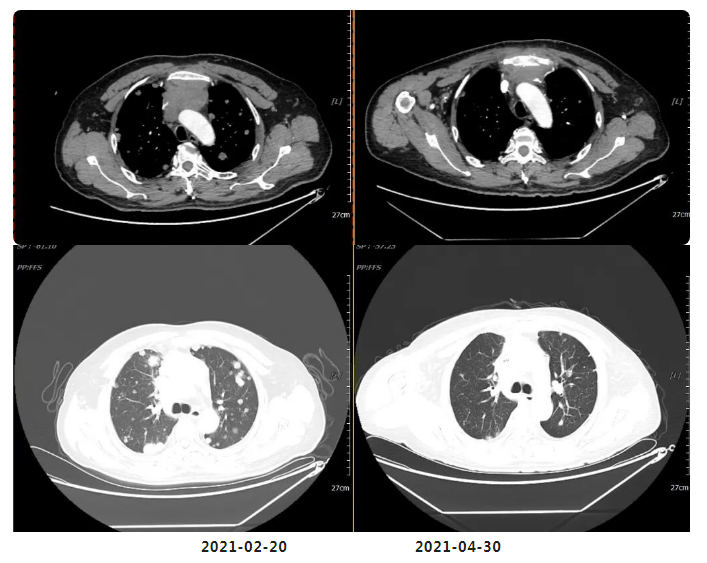

2周期化疗后复查疗效评价:PR

(四周期化疗后)复查疗效评价:SD(两肺及胸膜结节减少缩小;纵隔前间隙、纵隔内及两肺门淋巴结(2.5×3.0cm)较前部分缩小。